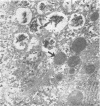

Type I mucopolysaccharidosis was diagnosed in a fetus by assay of the glycosaminoglycans of the amniotic liquor. Results are presented of biochemical and ultrastructural studies on the 18-week abortus. The evidence suggests that the liver is more severely affected than the central nervous system at this stage of gestation, and this finding agrees with the recent demonstration of the underlying enzyme defect of this disorder, with the corollary that many biochemical abnormalities previously noted in gargoylism must be pleiotropic effects of the mutant genotype.